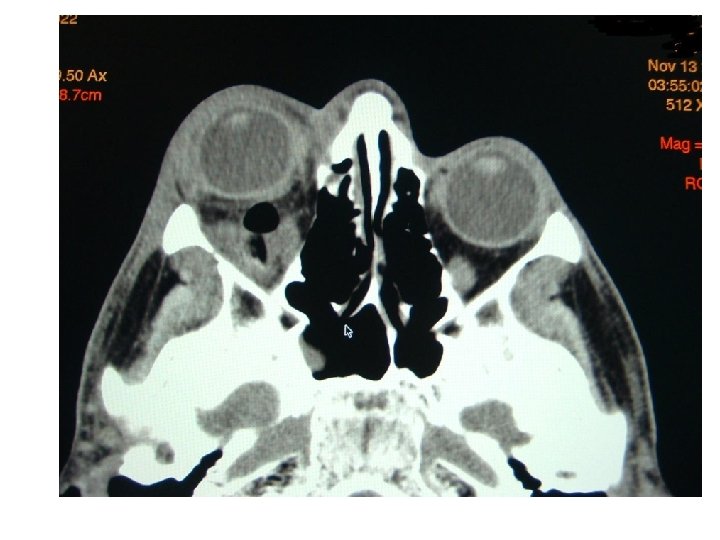

Orbital cellulitis Symptomatology • Post-septal infection • Eyelid edema and erythema • Proptosis and chemosis • Limited or no extraocular movement limitation • No visual impairment • No discrete abscess Low-attenuation adjacent to lamina papyracea on CT

• • Subperiosteal Abscess Pus formation between periorbita and lamina papyracea Displace orbital contents downward and laterally Proptosis, chemosis, ophthalmoplegia Risk for residual visual sequelae May rupture through septum and present in eyelids